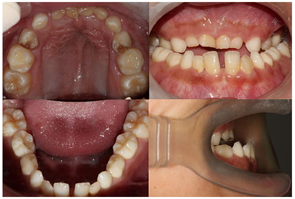

患者身高160cm,体重56kg,神志清,合作,智力正常。(1)口外检查:双肩陡峭下垂,肩关节活动度大,双肩可向前相互靠拢,两侧锁骨端缺如明显可见,手部可见远端指骨较短。头颅增大,面骨相对较小,眼距增宽,鼻梁塌陷;面型对称,颞下颌关节未见明显异常;面中份发育不足,III类骨性错

畸形(图1)。(2)口内检查:混合牙列,31、41、16、26、36、46萌出,37、47部分萌出,剩余乳牙滞留;54、64远中邻

面龋,探(-),叩(+),松0-I°,龈正常;全牙列反

,反覆盖10mm,双侧尖牙及磨牙近中关系;51、61扭转,上颌牙弓狭窄,腭盖高拱,31、41间可见间隙约5mm(图2)。(3)影像学检查:①曲面断层片示多数乳牙滞留,恒牙迟萌,多颗埋伏阻生多生牙。54、64远中邻面低密度影及髓,牙根吸收(图3);②CBCT示全口恒牙排列紊乱,上下颌骨内可见13颗多生牙,均位于恒牙胚舌腭侧,形态类似相邻恒牙胚(图4);③头颅侧位片示头颅侧位片示上颌骨发育不足(NA-Apo:-5.9°),下颌前突(SNB: 98.2°;FH-NPo:90.0°),骨性III类错